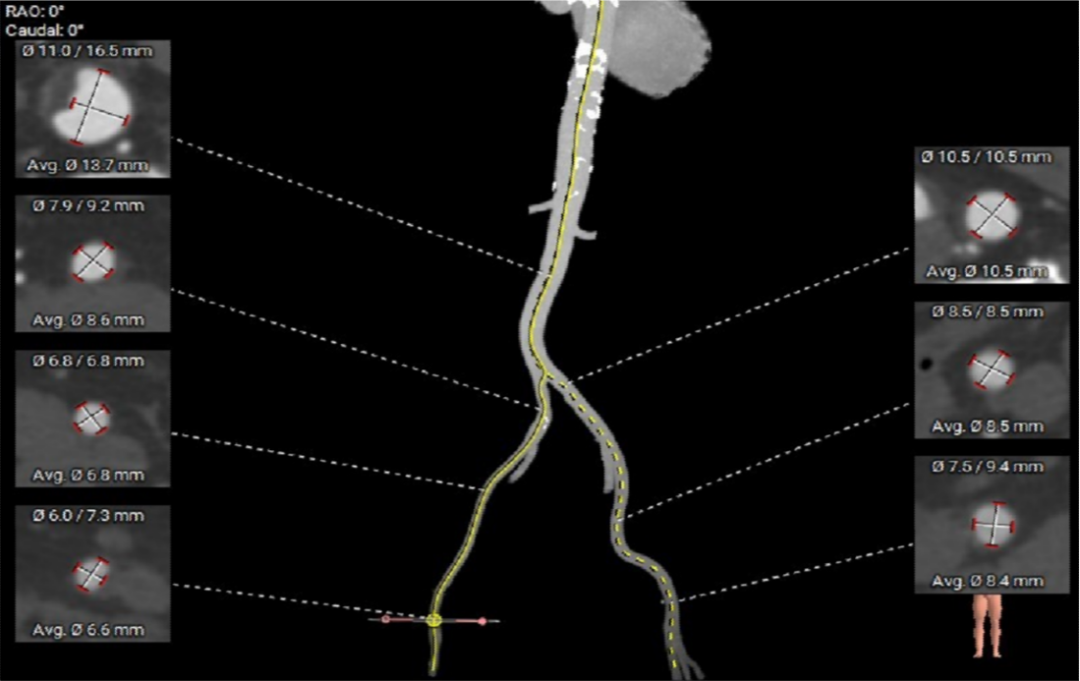

· 外周走行适宜,降主及胸主动脉存在散在钙化,左侧股动脉分叉稍高,血管内径可,血管内壁存在钙化和不规则纤维增厚。

外周血管及主动脉弓解剖